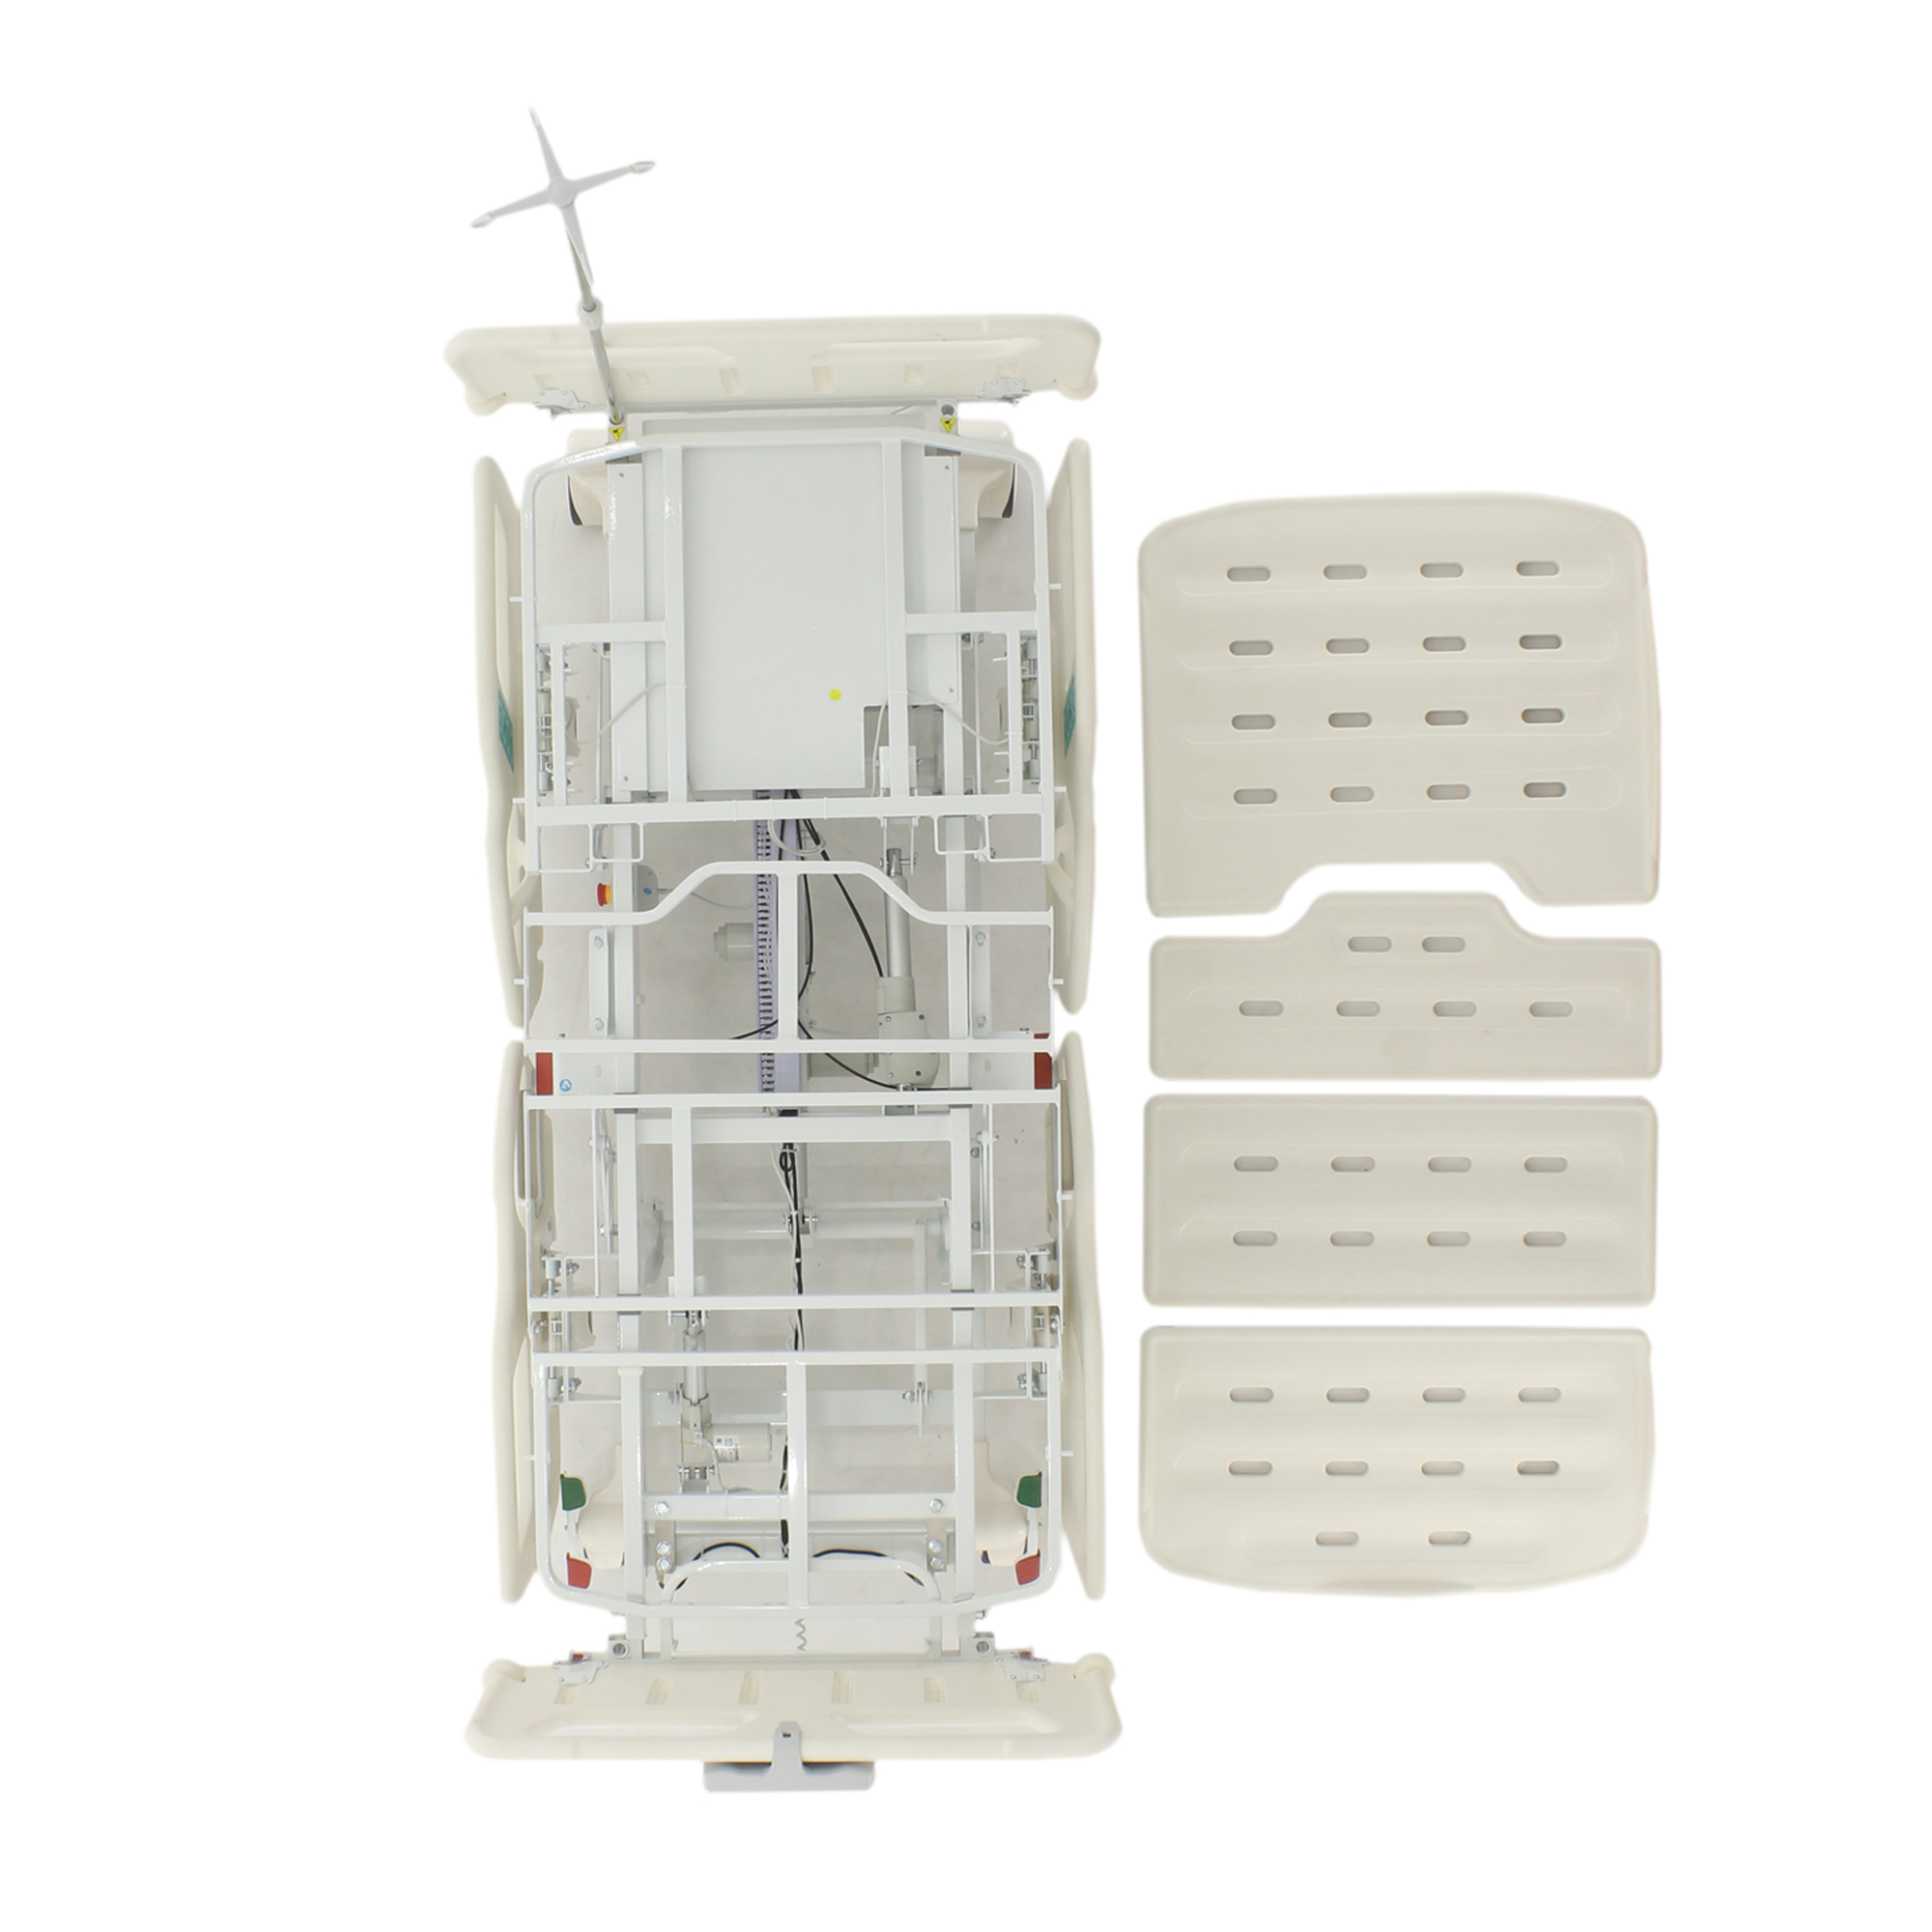

4 секции, из них 3 подвижных + удлинение

Ложе кровати: 192,5-220х90 см, съемные перфорированные секции из высокопрочного рентгенопрозрачного полипропилена

Каркас кровати: тройной, подвижный, из высокопрочной стальной профильной трубы с полимерно-порошковым покрытием, 4 отверстия для инфузионной стойки, с встроенным лотком для рентген-кассеты (34*59 см)

Комплектация: ложе, каркас, комплект спинок, матрас 4-х секционный + секция удлинения (190*87,5*10 см+20*87,5*10 см), 4 электропривода, комплект боковых ограждений, аккумулятор резервного питания (24В), ПУ для медперсонала, инфузионная стойка, крючки для мочеприемников - 2шт